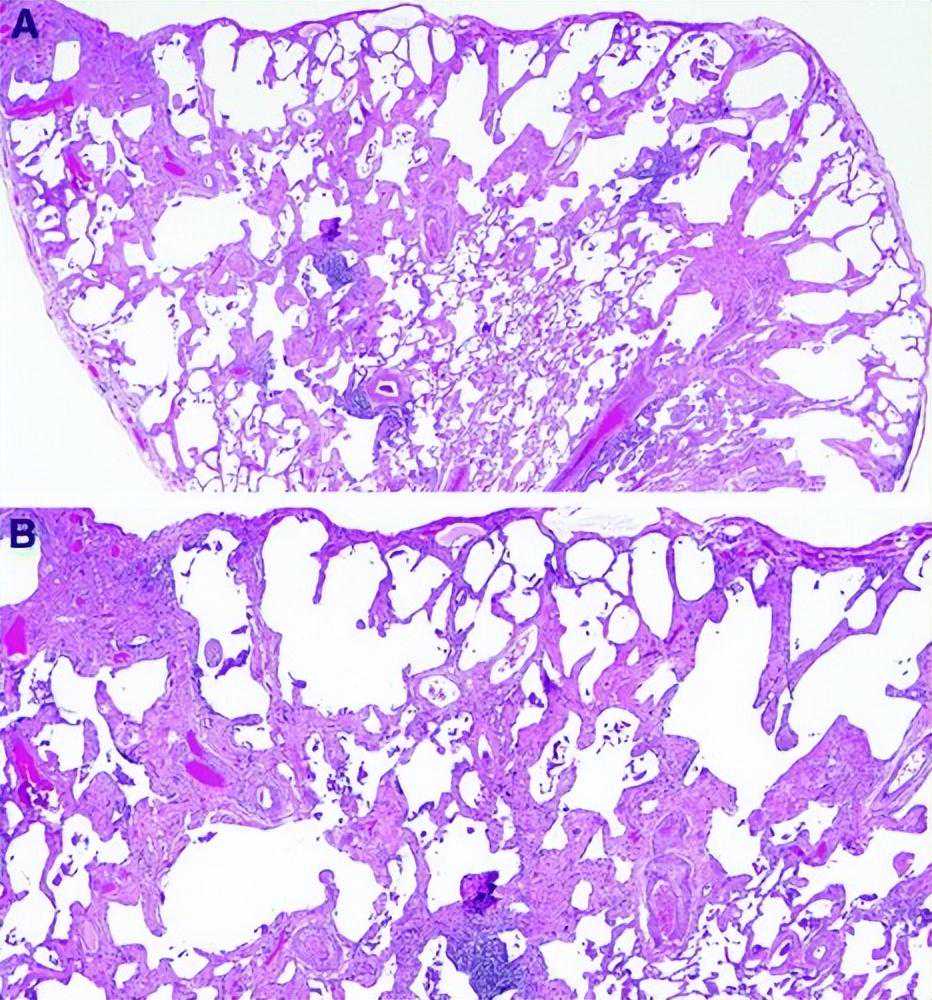

肺气肿是诊断CPFE的必要条件,它被定义为异常的、永久性的细支气管远端气腔增大,伴有气壁破坏,无明显纤维化(图10)[172-176]。对来自外植体肺切除术和尸检肺的仔细充气肺标本的形态学研究为肺气肿的解剖学定义提供了基础,并继续为我们了解其发病机制提供信息。然而,在活检中可以看到肺气肿和fILD共存,这种情况下病理学家需要记录肺气肿和fILD。小叶中央型肺气肿是一种上肺叶为主的肺气肿,由吸烟引起,在CPFE患者中常伴有间隔旁型肺气肿。肺气肿在外科肺标本中很常见,经常与其他吸烟相关的异常共存,包括呼吸性细支气管炎(RB)和SRIF[5,177]。

图10:重度吸烟者伴周围小细胞癌楔形切除术的小叶中央肺气肿。中倍镜显示气腔增大,细支气管壁破坏,可见游离结缔组织碎片。苏木精和伊红染色。